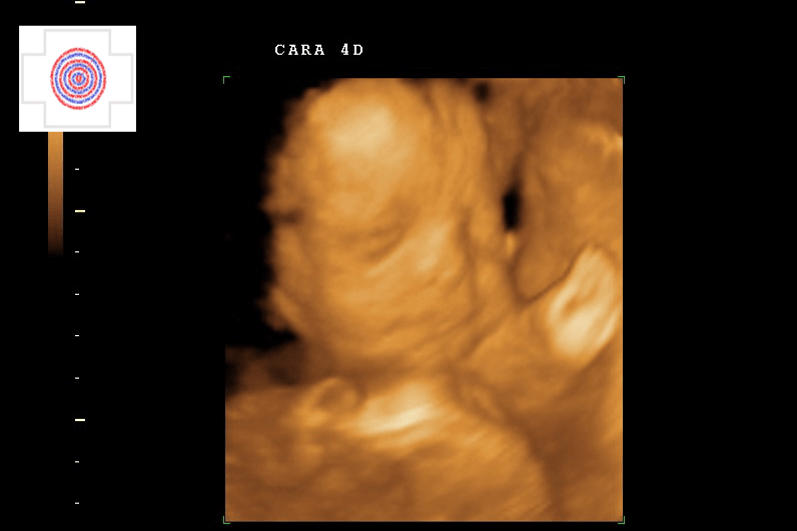

4D CARA IMAGEN CLARA, CARITA Y DEDOS

4D CARA SUPERFICIAL, BOCA, NARIZ, DEDOS